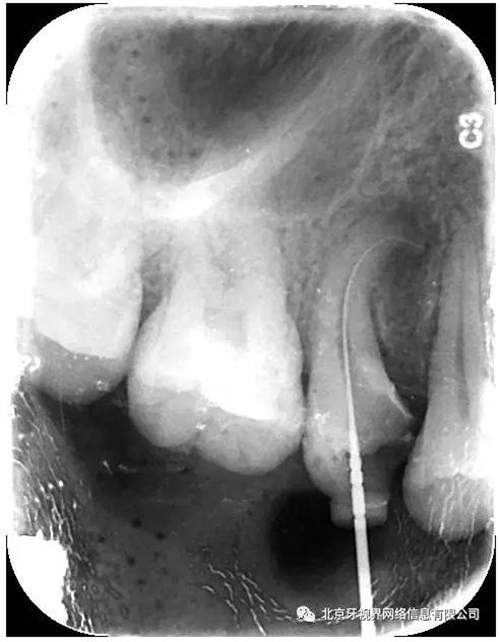

輔助檢查:15根尖周低密度影像,根尖1/3向近中彎曲

(1)15根尖周低密度影像結(jié)合查體診斷根尖周炎,根尖中下段明顯彎曲,能否疏通全長,順利抵達(dá)根尖區(qū)為術(shù)者首要考慮。

4.此例病例中,術(shù)前分析后,采取先解放其中上段后,10#擴(kuò)大器預(yù)彎緩慢前行,抵達(dá)根尖區(qū)。